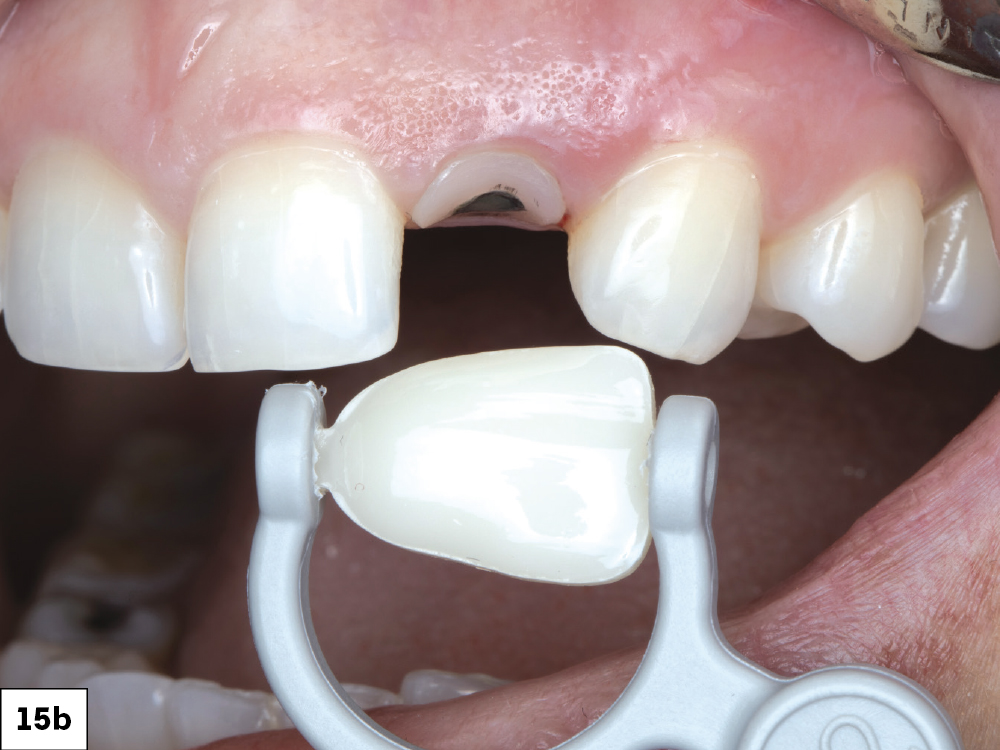

The patient returned three months later for an evaluation. The gingival architecture was observed to be well-maintained and healed effectively. A shade map of the tooth was created and documented.

Figures 15a, 15b: The patient returned three months later for an evaluation. The gingival architecture was observed to be well-maintained and healed effectively. A shade map of the tooth was created and documented.